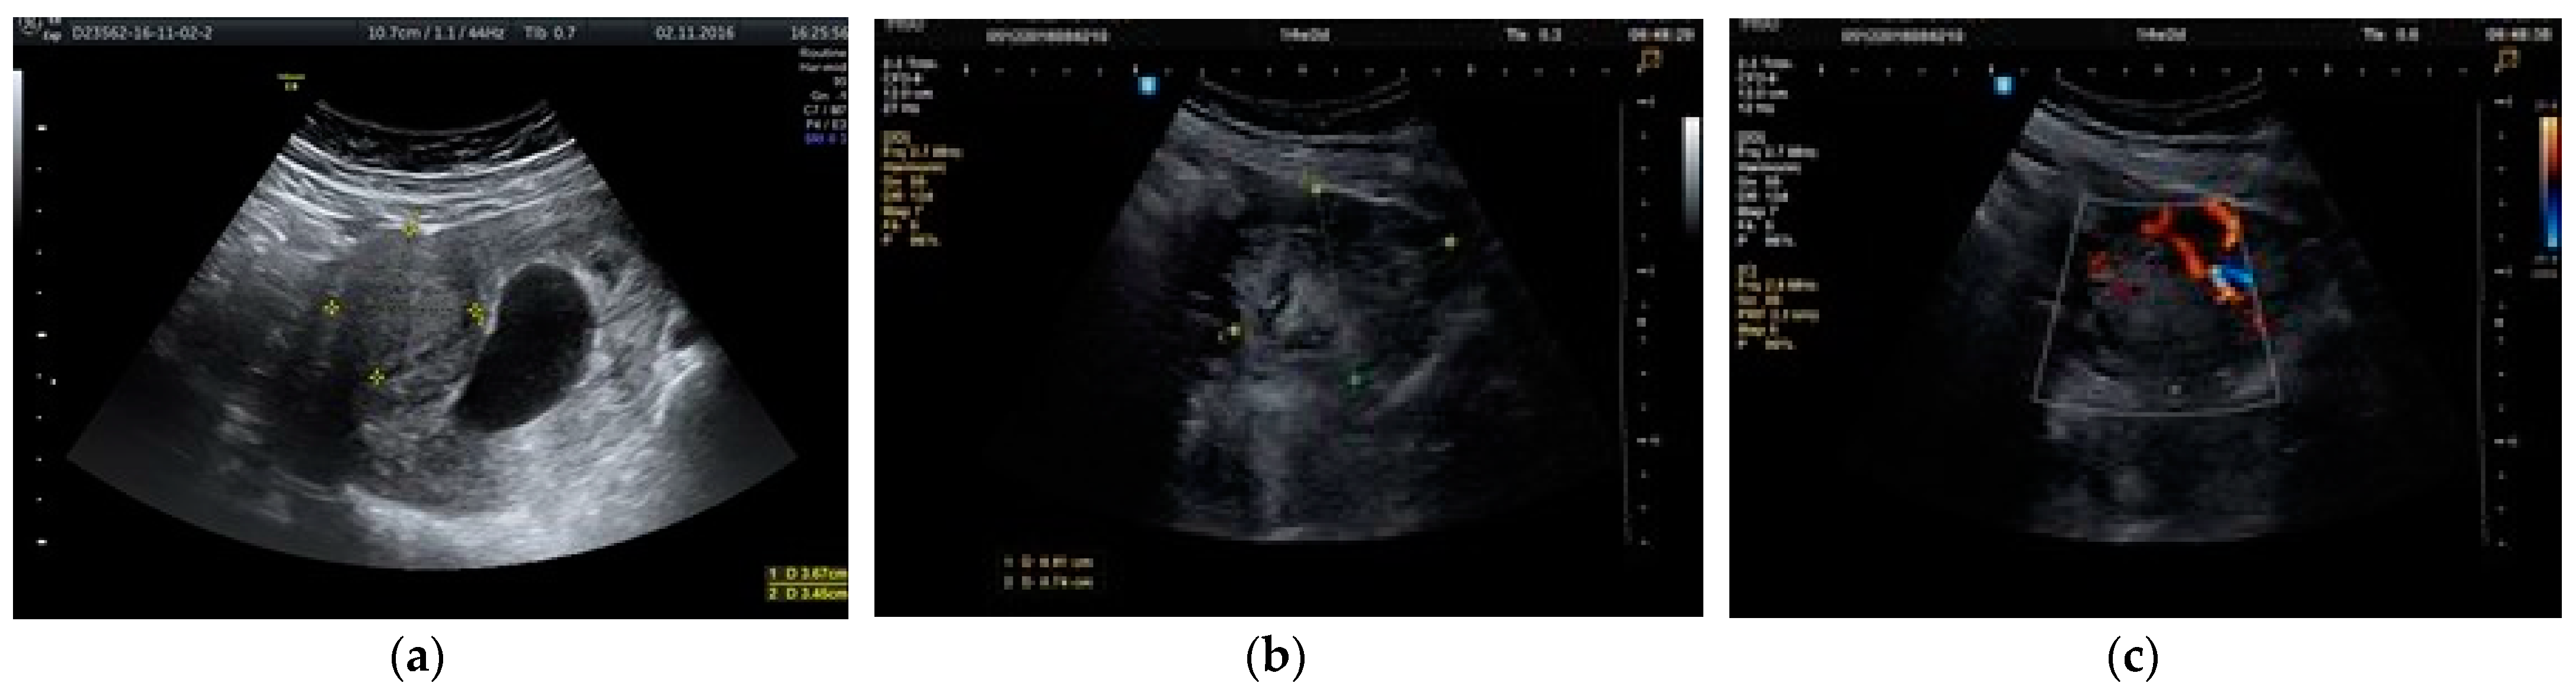

2. Materials and Methods

3. Results